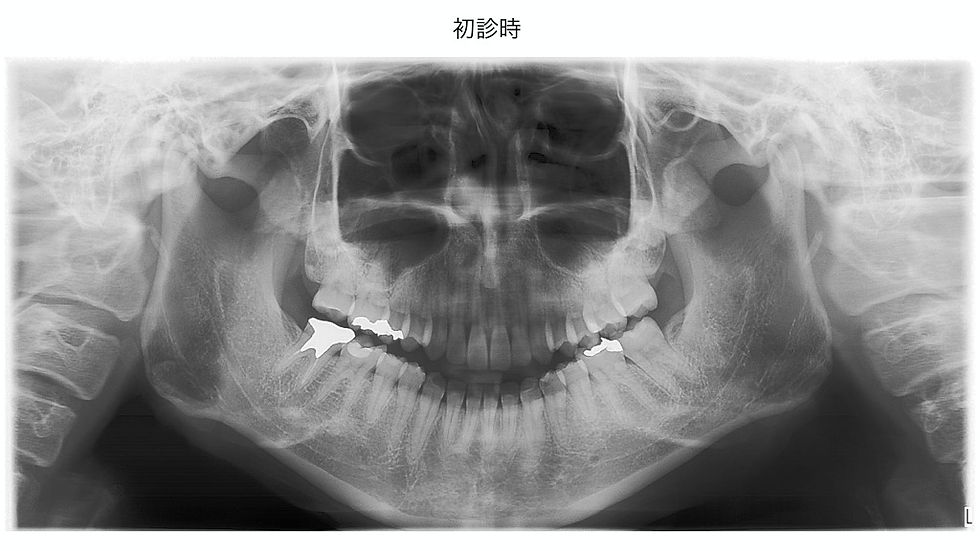

初診時